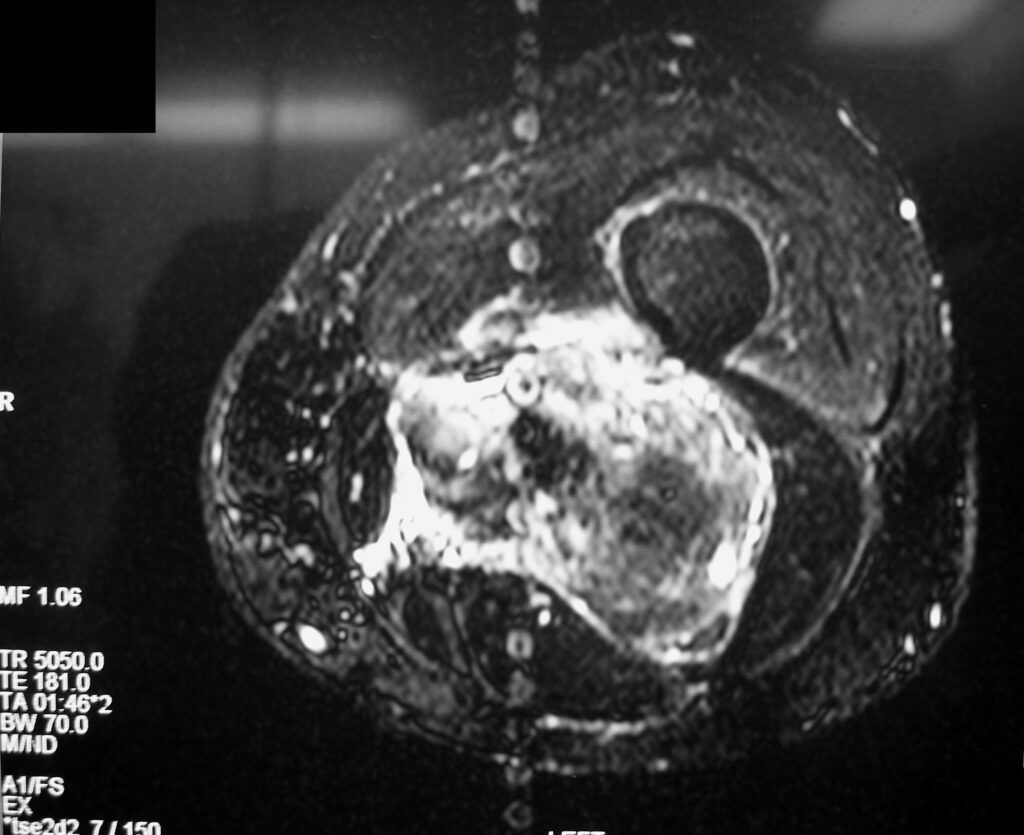

On radiographs, extraskeletal osteosarcomas show a mass with soft tissue density and variable amounts of mineralization best visualize on an Xray or CT scan, which may appear as a dense, cloudlike area (Fig. 1-3). A well circumscribe heterogeneous mass, Isointense to muscle on T1-weighted images and isointense to mildly hyperintense on T2-weighted images (Fig. 4-7). Mineralized areas will be dark on T1 and T2 weighted images.

Fig. 6 & 7: MRI of an Extraskeletal Osteosarcoma Axial T2 –weighted fat-suppressed image shows a heterogeneous and hyperintense signal in the posterior compartment of the thigh, central hypointense areas concordant with necrosis and mineralization. Axial T2- weighted fat suppress contrast enhanced image (Fig. 7) demonstrates an enhancement area in the posterior compartment of the thigh.